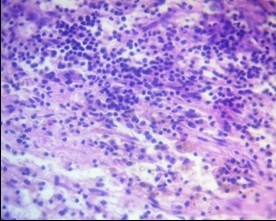

In cases of anaplastic astrocytoma, anaplastic oligodendroglioma, and especially glioblastoma, a significant increase in immune cell density was observed: foci of dense lymphocytic infiltration were detected, often with the participation of neutrophils, forming a mixed leukocyte population (Fig. 14). These changes were associated with areas of necrosis, microvascular proliferation, and pronounced perifocal edema, reflecting activation of the innate and adaptive immune response.

Figure 14. Perivascular lymphoinfiltration zone of glioblastoma. Dense lymphocytic/leukocyte infiltration. H&E, ×400.

E-eosin, H- hematoxylin